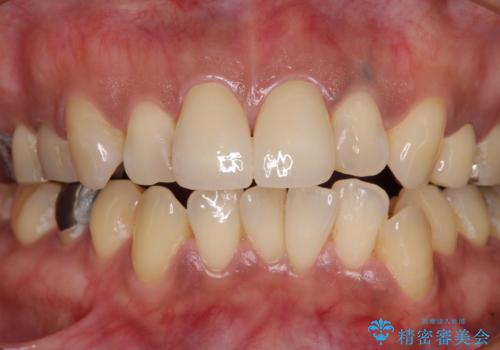

色彩や形態が大きく改善されたことはもちろん、虫歯によってしみていた症状もなくなり、患者様には大変満足していただきました。